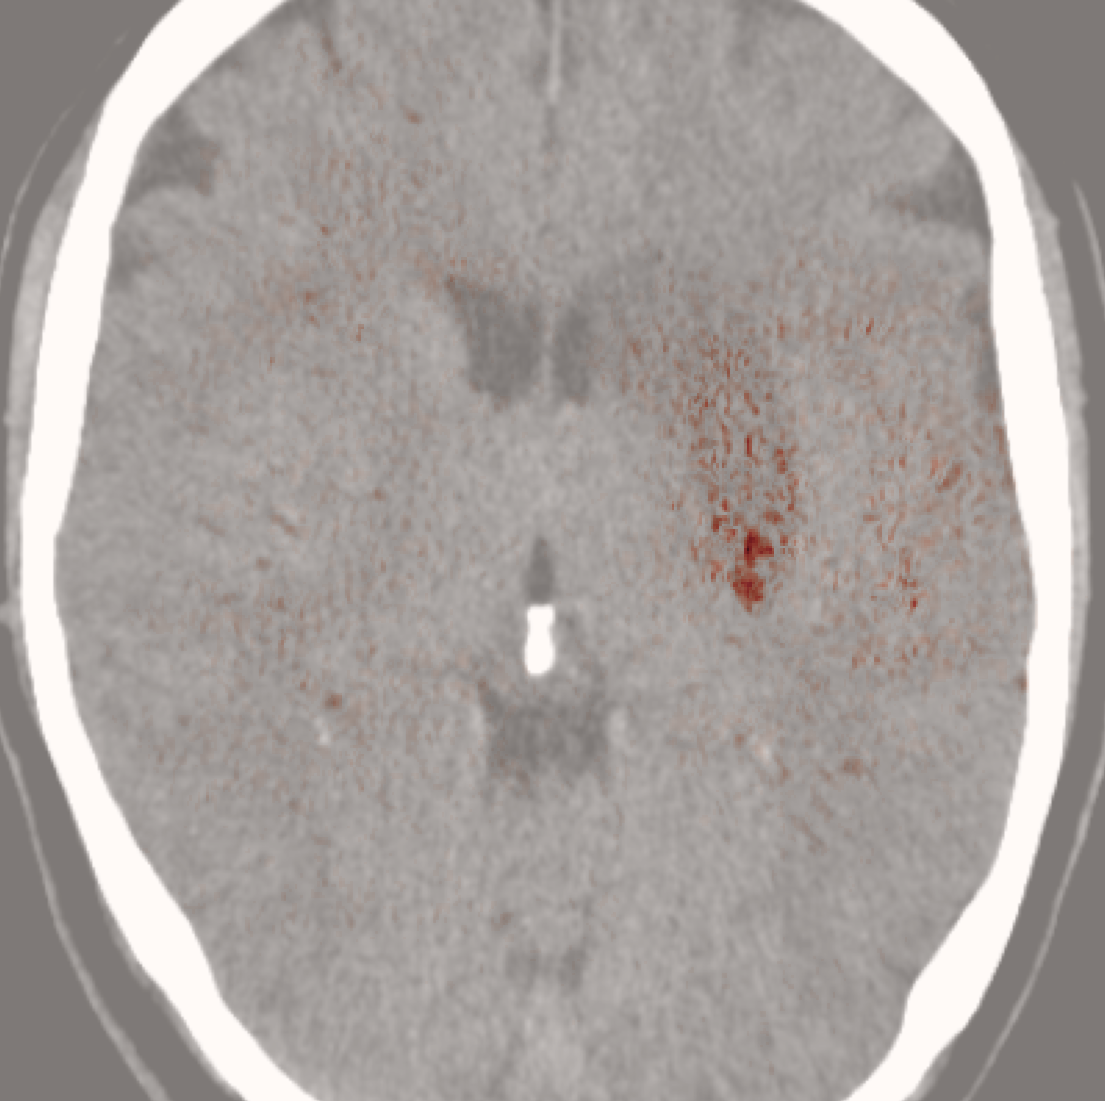

While ACAT revolves around generating counterfactuals, its primary strength lies in accurately identifying pathological regions, which are subsequently employed in a classification pipeline. On the other hand, it falls short in producing credible counterfactual examples, an issue we aim to address in this study. An illustration of this phenomenon is depicted in Figure 2, where we can observe how ACAT is able to generate a saliency map that approximately identifies the pathological region (e, bottom row). However, in the counterfactual example, the lesion remains visible (e, top row). In contrast, our approach not only refines the saliency map but also generates a counterfactual image where the pathology is completely eliminated (f).

4.3 Counterfactual Examples

In Figures 2 and 4 we display examples of healthy images and anomaly maps obtained with the different approaches. We can observe that f-Ano GAN is not able to generate credible counterfactuals and generally produces images of poor quality and unrealistic appearance. On the other hand, the approaches based on diffusion models are able to create more high-quality results. However, the ones obtained with CG and CFG seem to present some artifacts, which may not only impact the realism of the counterfactual examples but also the precision of the anomaly maps obtained from them. In order to better quantify the capability of these methods to accurately segment pathological areas, we compute the Dice scores of the anomaly maps they generate.